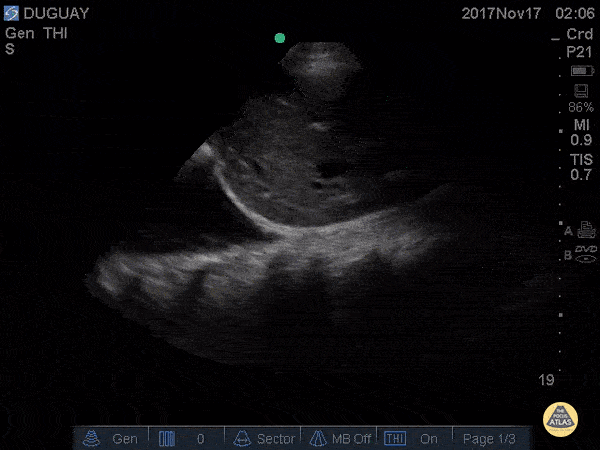

RUQ scan with large R pleural effusion. Spine sign+ (clear view of several thoracic vertebrae through the effusion) Gary Duguay